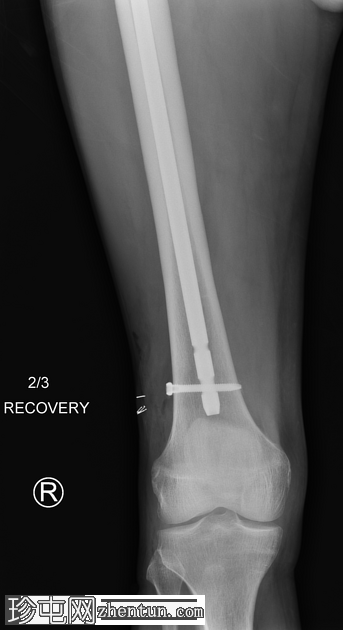

右侧髓内钉近端骨折(位于拉力螺钉孔位)。

空心髋螺钉组件完好。

股骨转子间骨折延伸至股骨近端转移灶,小转子粉碎。